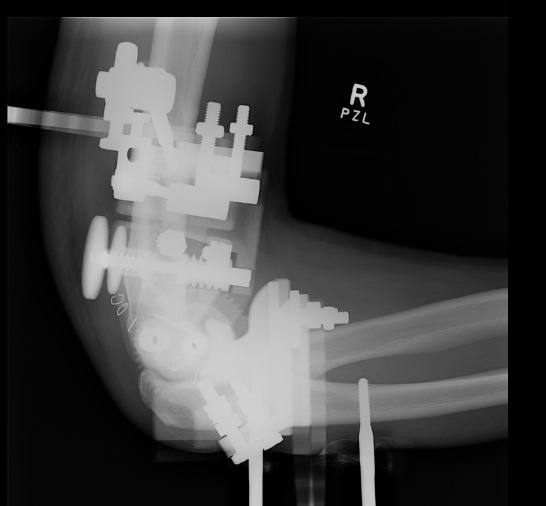

Internal joint stabilizer

IJS Elbow Stabilization System

Concept

Dynamic internal fixator

Technique

Crescenzo et al JSES Rev technique PDF

Results

- 24 patients treated with IJS-E

- 1/24 redislocated - coronoid deficient

Heifner et al J Hand Surg Glob 2023

- systematic review of 171 elbow dislocations treated with IJS-E

- implant failure 4%

- recurrent instability 4%